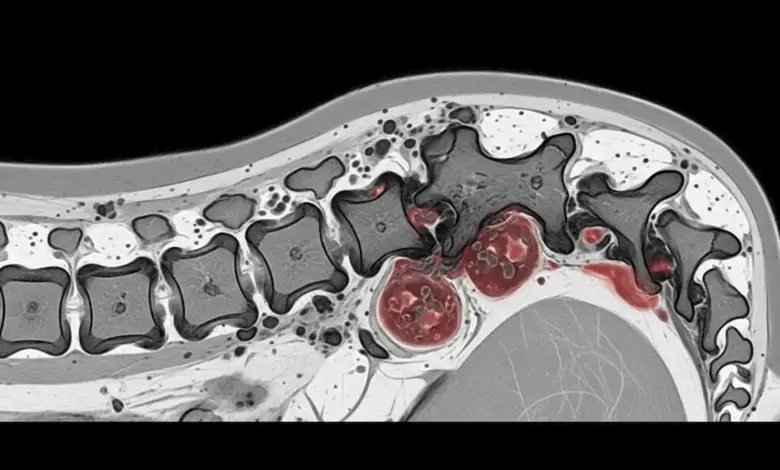

Mal de Pott, também chamado tuberculose espinhal ou espondilite tuberculosa, é uma infecção crônica da coluna, e costuma comprometer principalmente os segmentos torácico e lombar.

A doença começa no corpo vertebral, pode avançar para o disco e formar abscessos paravertebrais.

- Exames de imagem: radiografia, tomografia computadorizada e ressonância magnética (método mais sensível para partes moles, disco e medula).